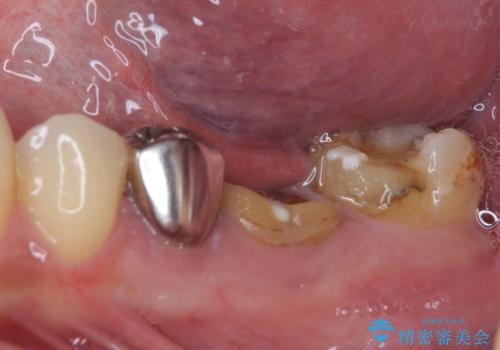

欠損と治療途中の奥歯 インプラント治療と補綴治療

- 下顎左右の奥歯を治療途中で放置してしまっているとのことで来院された患者様です。

欠損部はインプラントによる補綴治療を、土台の外れてしまった歯は、根管治療を行った上で、補綴治療を行うこととしました。

骨格的に下顎が大きく上顎が小さいため、奥歯に力の負担のかかりやすい咬み合わせであるので、治療後は睡眠時にマウスピースを装着することで、セラミッククラウンやインプラント、治療をしたご自身の歯が長持ちするよう指導しています。